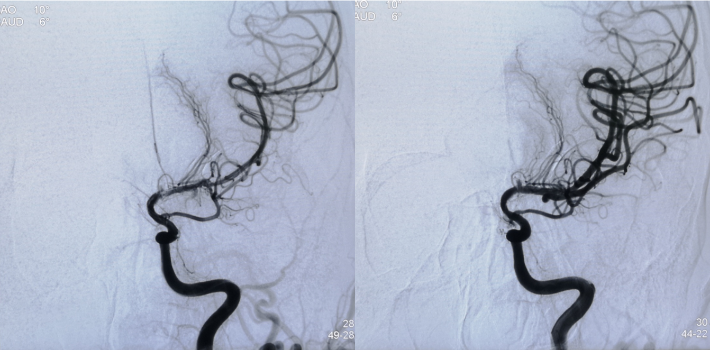

此次入院后,即予行全脑血管造影术,示左侧颈内动脉虹吸段重度狭窄。予患者家属充分沟通后,进一步行左侧颈内动脉虹吸段狭窄球囊扩张+支架植入术。

DSA

--DSA显示左侧颈内虹吸段狭窄约72%。前交通开放,右侧大脑前动脉通过前交通动脉向左侧大脑前动脉、大脑中动脉供血区有代偿供血。